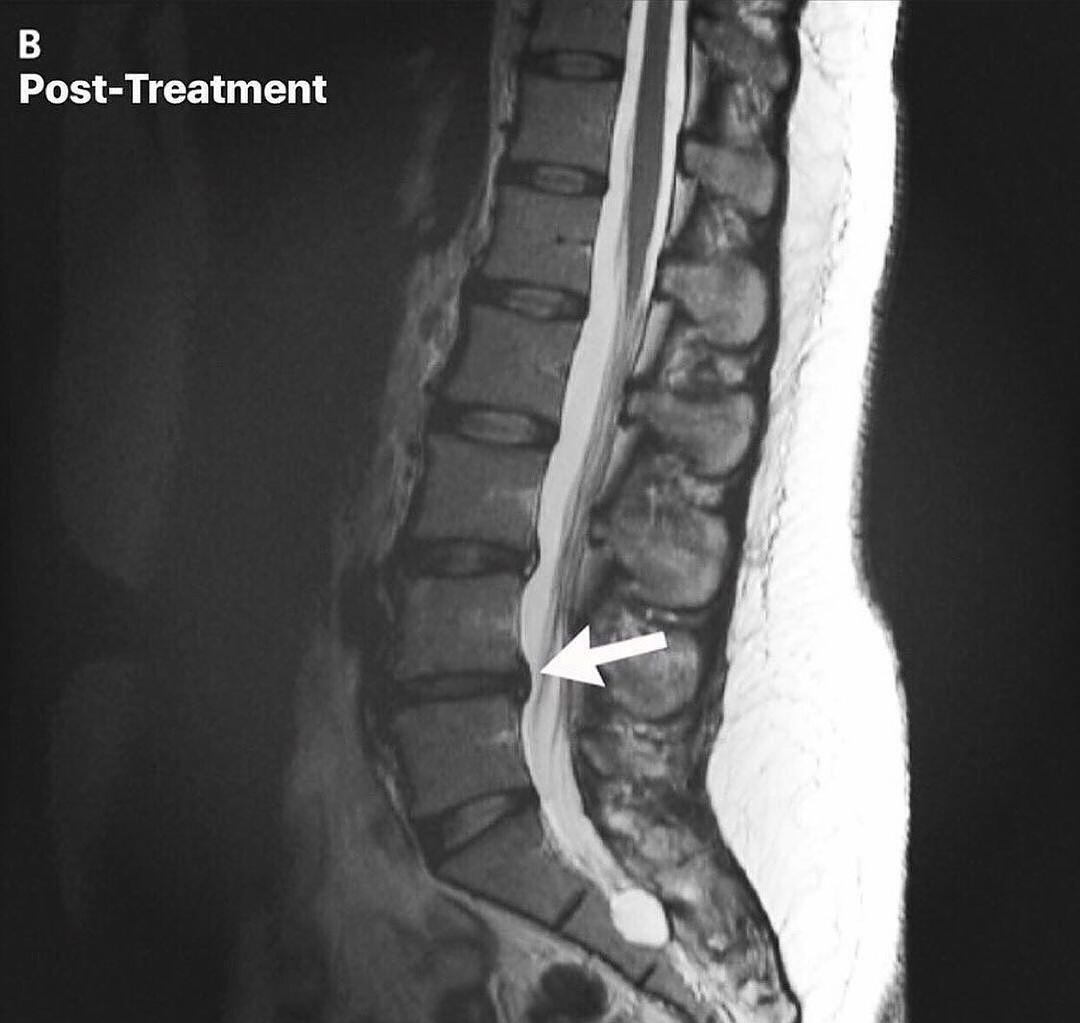

Spinal disc injuries require more than symptom-based care. Our spinal disc rehabilitation approach in Inver Grove Heights focuses on restoring movement, reducing pressure on the disc, and improving how the spine and nervous system work together over time. Care is guided by imaging, clinical findings, and measured progress, not guesswork or force.This care is designed for people dealing with disc herniations, disc bulges, sciatica, chronic back or neck pain, and those who have not improved with traditional chiropractic care. It is also appropriate for individuals looking for non surgical disc care before considering injections or surgery.